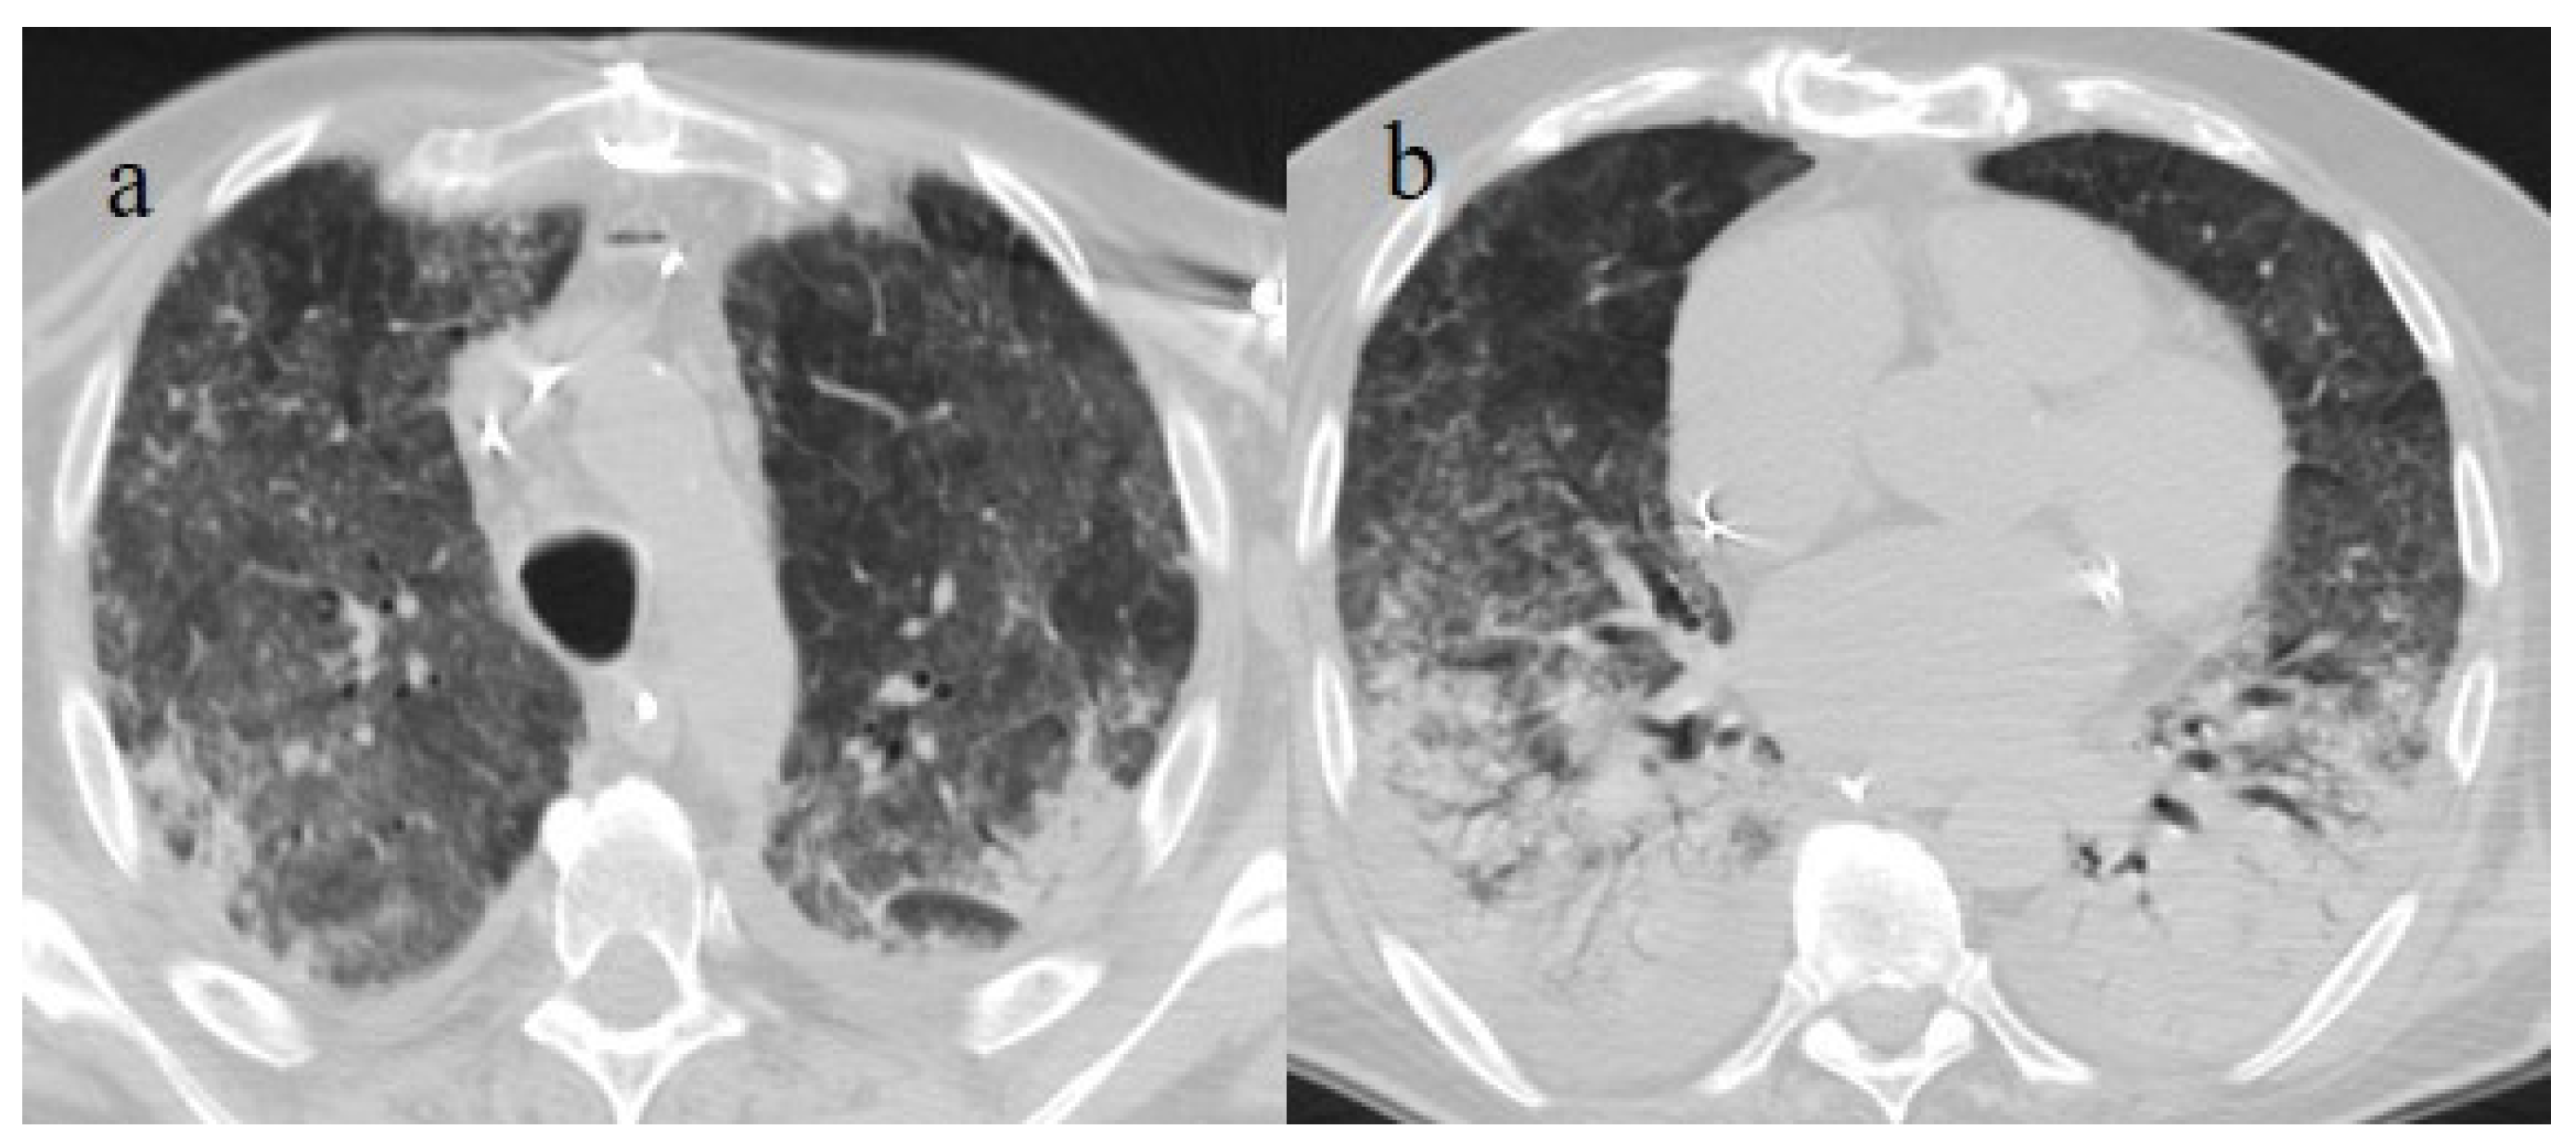

| Typical Appearance | GGOs with a crazy-paving pattern and consolidations in a peripheral and posterior or central-peripheral distribution; multilobar involvement; vascular enlargement, the halo and reversed halo sign; subpleural and parenchymal bands; and architectural distortion. They were predominant since the Delta wave. |

| Typical findings of interstitial pneumonia with peripheral or peripheral central distribution from the wild/type variant since Delta variant |

| Possible severe forms of COVID-19 pneumonia in breakthrough infections in the elderly and in patients with an immunosuppressive state | |||